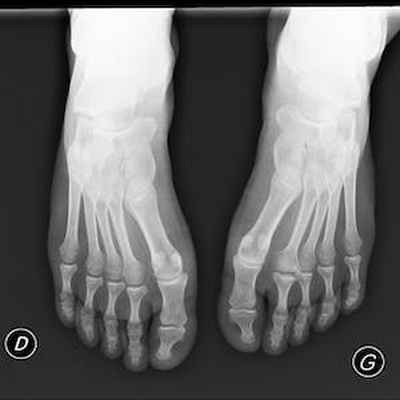

Боль в переднем отделе стопы правой ноги у пациентки 19 лет, в области головки 2-ой плюсневой кости.

Головка 2-ой плюсневой кости выглядит сплюснутой и расширенной с правой стороны в связи с болезнью Фрейберга.

Отсутствие внутрикостной отёчной инфильтрации по краям суставной щели плюснефалангового сустава. Напротив, следует отметить наличие внутрисуставного выпота.

Отсутствие бурсита между головками плюсневых костей или под ними.

Не обнаружено невромы Мортона или тендовагинита.

Радиодиагностическое исследование показывает линию перелома, более или менее заметную, расширение суставной щели. Головка сплюснутая и расширена в развитой стадии некроза.

Рентген болезни Фрейберга:

- На картинке выше мы видим остеонекроз (отмирание костной ткани) второй плюсневой кости. Характерный признак болезни Фрейберга.